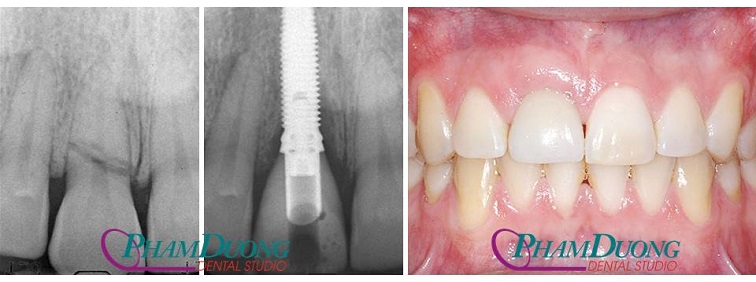

(Trường hợp chân răng bị gãy do tai nạn được cấy ghép Implant)